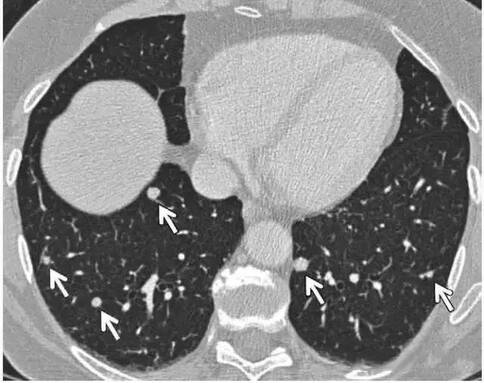

介紹2:多發(fā)性非鈣化實(shí)性結(jié)節(jié)

? ?對(duì)于至少有1個(gè)結(jié)節(jié)直徑>6 mm的多發(fā)性鈣化實(shí)性結(jié)節(jié),建議在3~6個(gè)月時(shí)進(jìn)行隨訪,然后根據(jù)風(fēng)險(xiǎn)在18~24個(gè)月考慮是否進(jìn)行第2次隨訪(1B等級(jí);強(qiáng)介紹,中質(zhì)量證據(jù))。